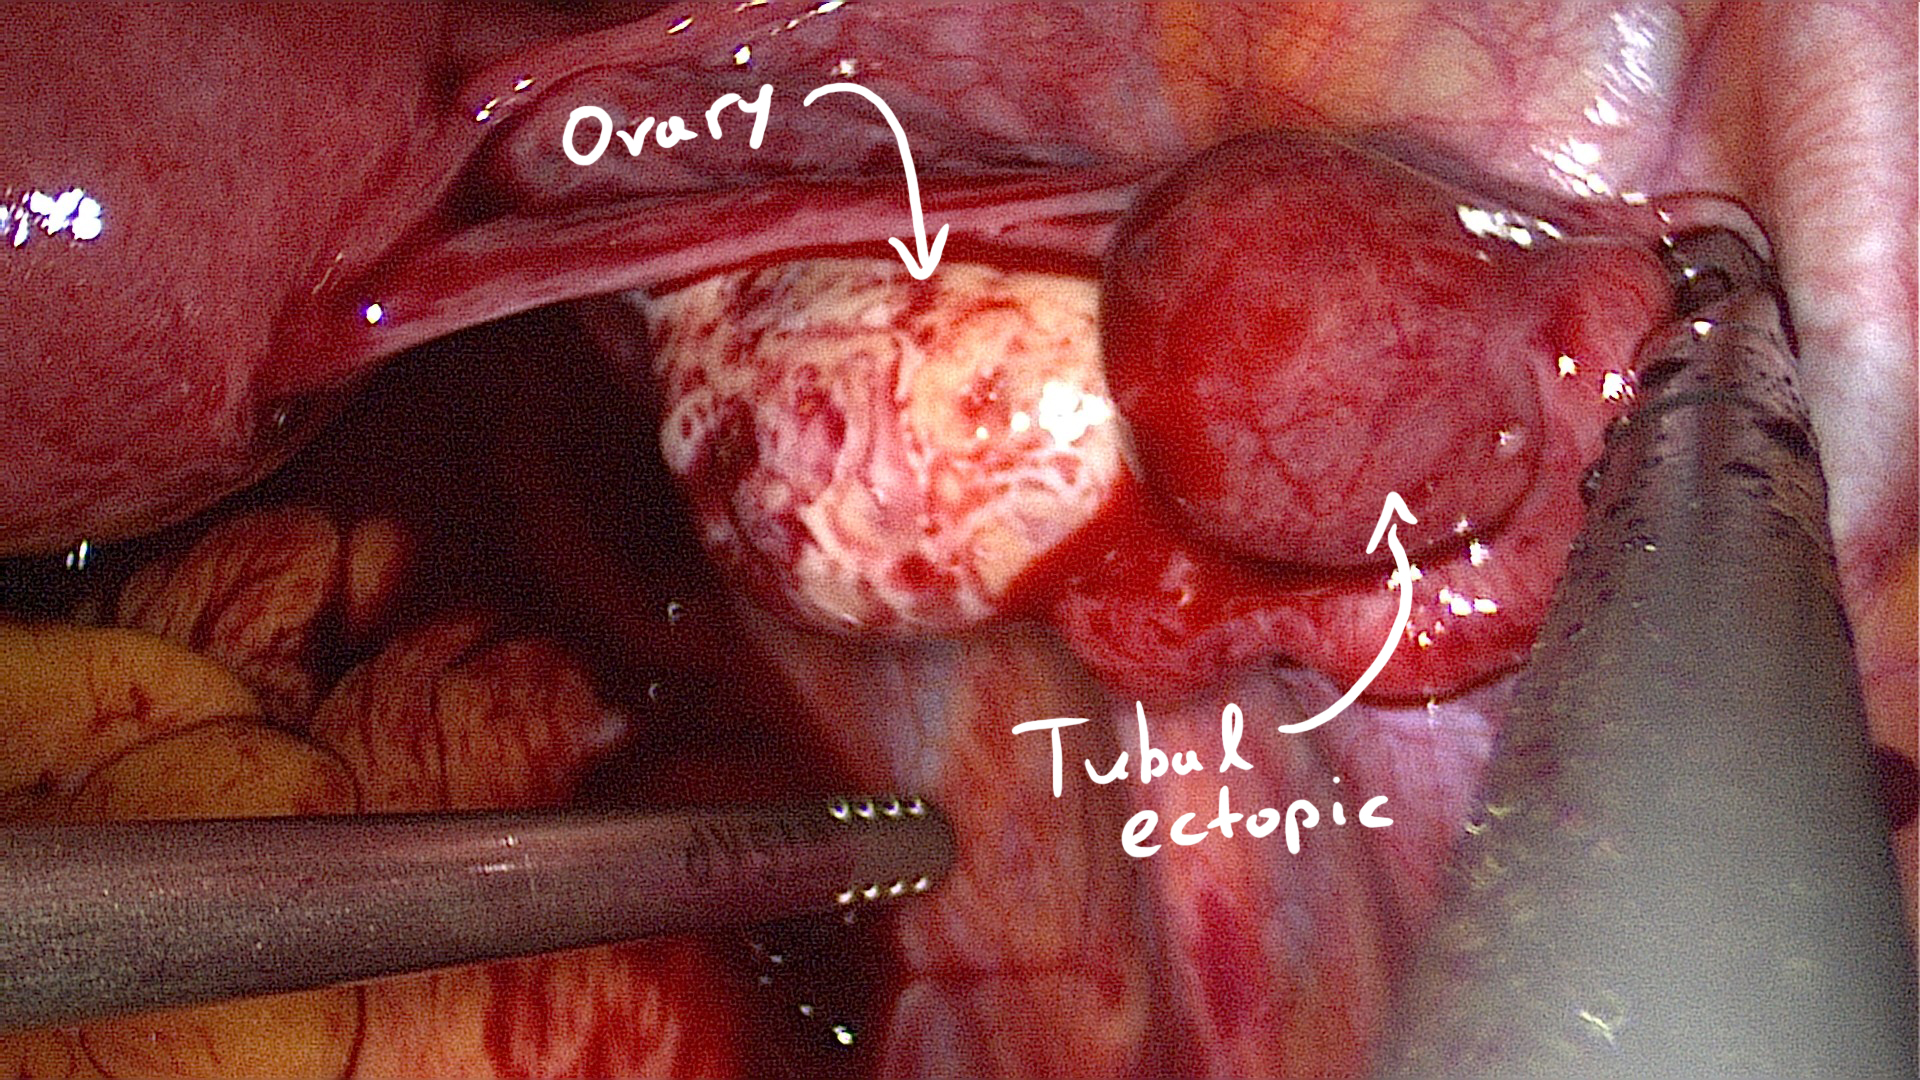

Tubal ectopic pregnancies should be identified by visualising an adnexal mass that is separate from the ovary (Elson CJ et al., 2016). The presence of this inhomogeneous mass which is clearly not a part of the ipsilateral ovary or of the uterus is called the blob sign (Nadim B. et al, 2017).

Tiny tubal ectopic.